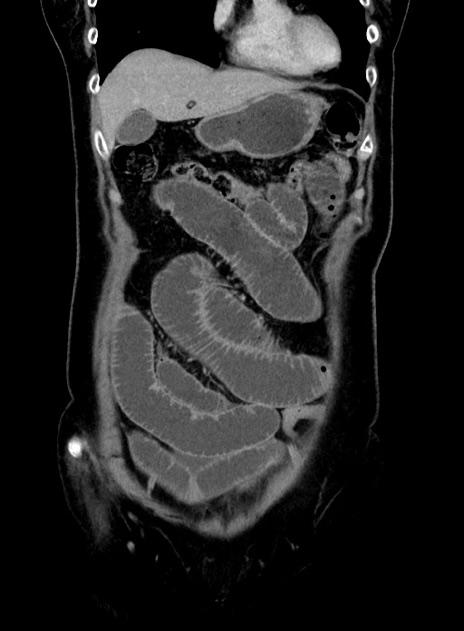

症例9(冠状断像)

【症例】 60歳代女性

【主訴】むかつき、みぞおちの痛み

【現病歴】3日前よりむかつきがあり、食事がとれない。

【既往歴】糖尿病

【身体所見】発熱なし、心窩部圧痛軽度あるも、腹膜刺激症状なし。

【データ】WBC 7400、CRP 1.92